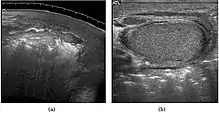

Fig. 6. Mature cystic teratoma. (a) Composite Image. Mature cystic teratoma in a 29-year-old man. Longitudinal sonography image of the right testis shows a multilocular cystic mass. (b) Mature cystic teratoma in a 6-year-old boy. Longitudinal sonography of the right testis shows a cystic mass contains calcification with no obvious acoustic shadow.